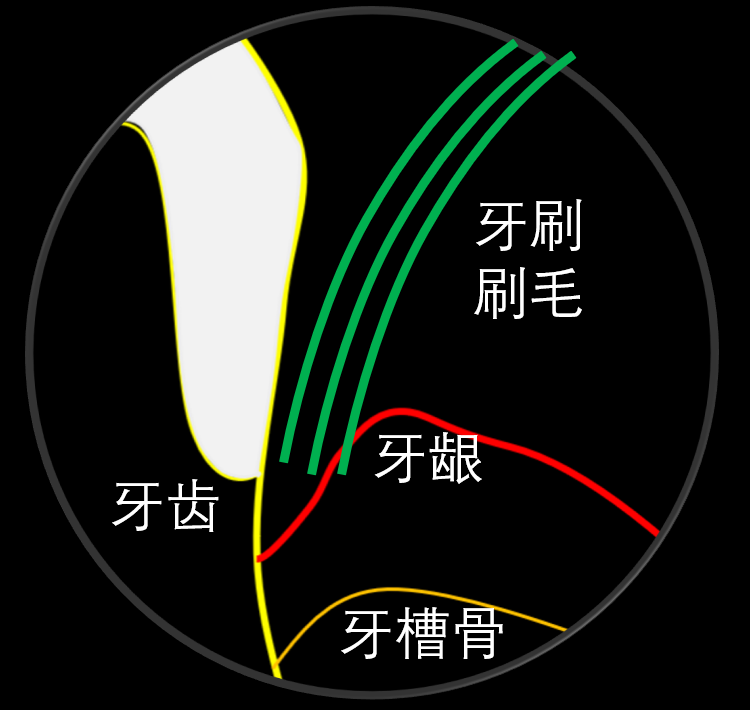

图5. 龈沟内的清洁。对于患者来说,刷牙的一个重点区域就是龈沟。应选择软毛牙刷,牙刷的刷毛尖端可以部分进入龈沟,从而清洁龈沟内的软垢。详细的刷牙方法可以参考巴氏刷牙法。